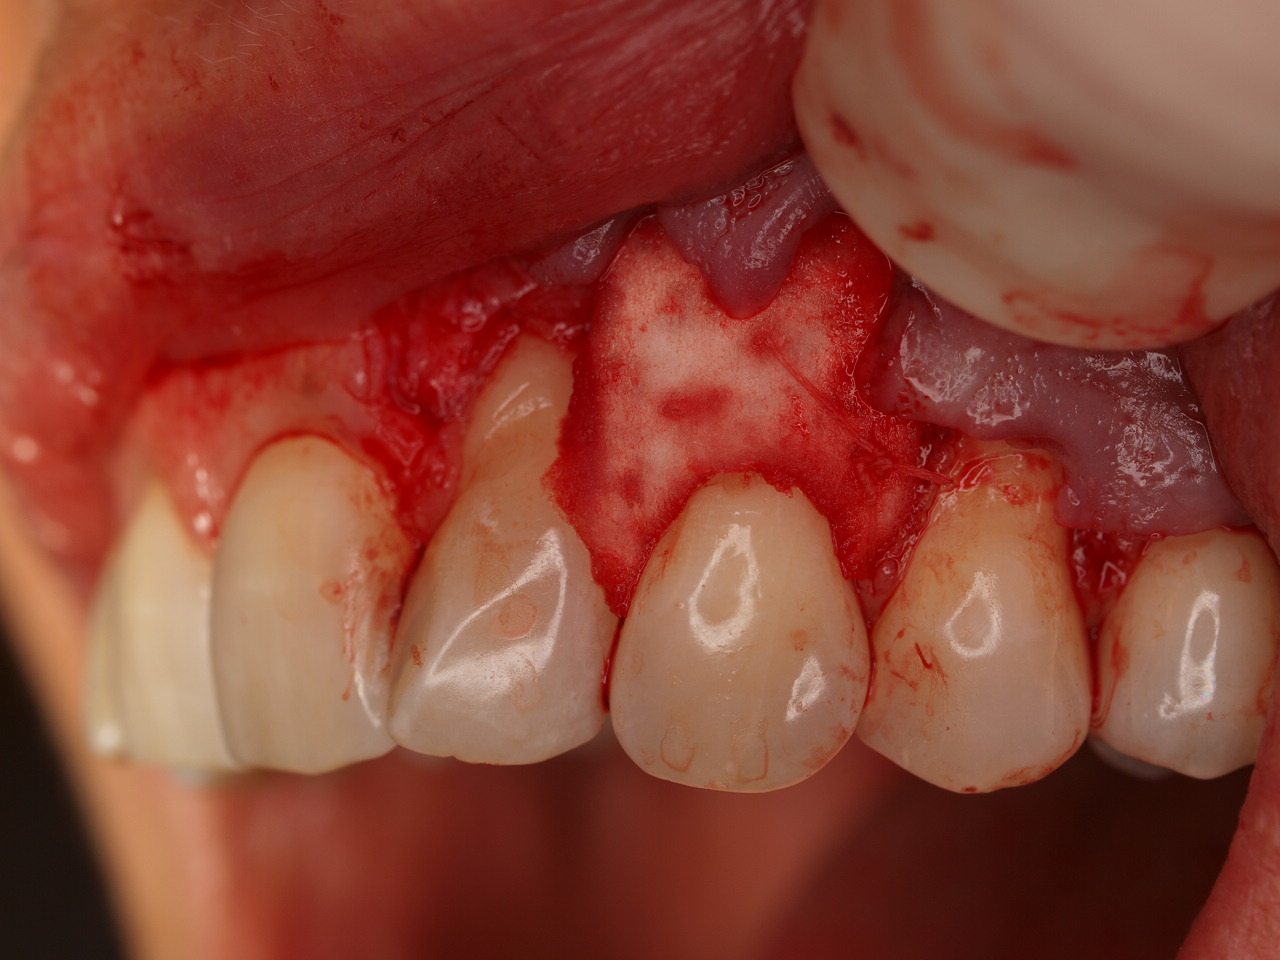

Multiple gingival recessions treated by MCAT with mucoderm® and Straumann® Emdogain® (2) - Rathe

Pre-operative clinical situation. Shallow multiple adjacent gingival recessions in the first quadrant.